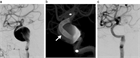

1. 未破裂脳動脈瘤の診断は、カテーテル法によるDSA:digital subtraction angiographyおよびその3次元血管撮影像がゴールドスタンダードである。3D-CTA:3次元ヘリカルコンピュータートモグラフィー、MRA: magnetic resonance angiographyなどは低侵襲な代替え診断法として未破裂脳動脈瘤の診断および治療に用いることが妥当である(推奨度1、J)